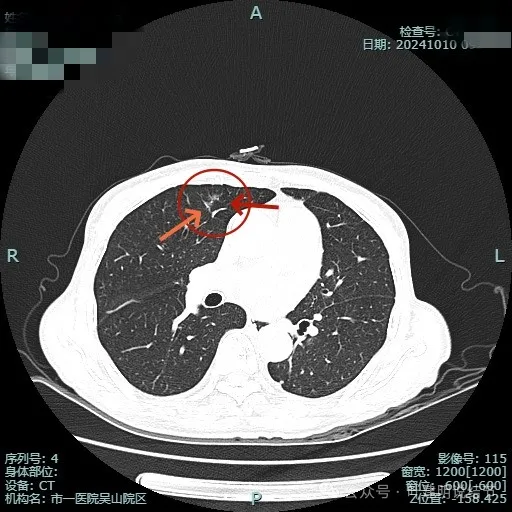

再看2024年10月在杭州市肿瘤医院复查的影像:

病灶出现,表面不平分叶状,有异常增粗血管贴着病灶,整体轮廓较清,看着非常不舒服。